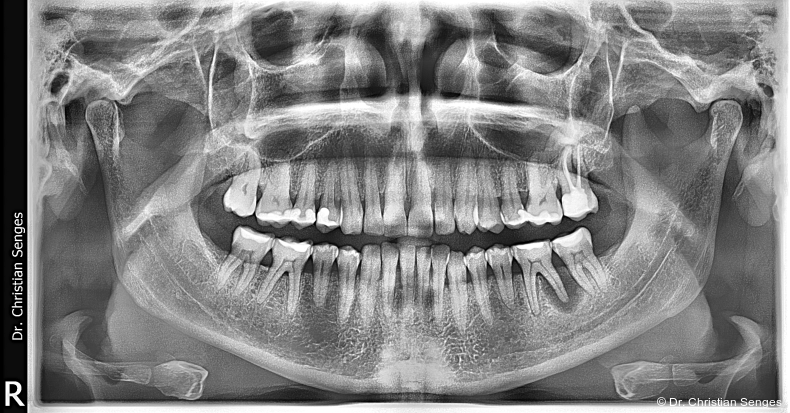

Eine 46-jährige Patientin stellte sich im Mai 2023 in unserer Praxis vor und klagte über Zahnfleischprobleme, insbesondere im Molarenbereich des Unterkiefers links. Ihre psychische Verfassung war instabil aufgrund eines unerfüllten Kinderwunsches, trotz mehrerer Embryonentransfers in den vergangenen Jahren. Die klinische Untersuchung ergab erhöhte Sondierungstiefen von 5 bis 8 mm an den Zähnen 36 und 37, einschließlich Pusaustritt. Der Parodontale Screening-Index (PSI) ergab die Werte 3-4-4-4-4-4. Die Vitalität aller Zähne, insbesondere von Zahn 36, war positiv. Eine anschließende Panoramaschichtaufnahme zeigte generalisierten horizontalen Knochenabbau im Ober- und Unterkiefer mit einer periradikulären Aufhellung an der distalen Wurzel von Zahn 36 sowie eine freiliegende Bifurkation an Zahn 46 (Abb. 1). Die Patientin wurde über die negativen Auswirkungen der Entzündung an Zahn 36 und der unbehandelten Parodontitis für den geplanten Embryonentransfer in naher Zukunft aufgeklärt.